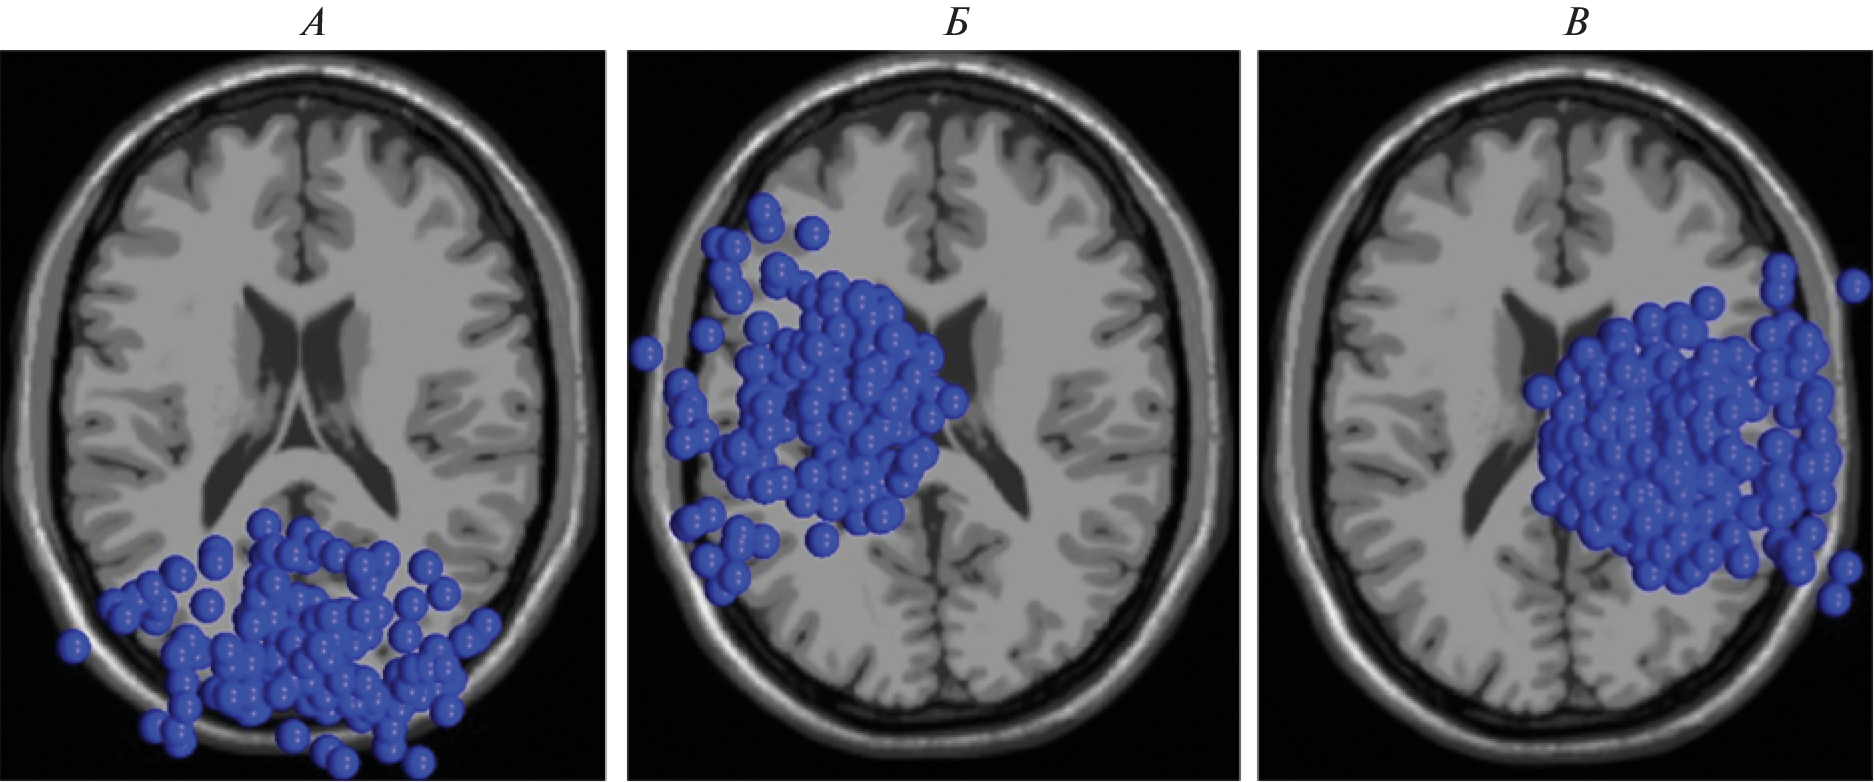

The aim was to study the oscillatory dynamics accompanying the processes of interaction with the virtual character and the localization of the revealed effects. 42 subjects (of which 25 are women) aged 18 to 41 years took part in the study. During the EEG recording, the subjects had to interact with the virtual character by choosing one of three options (“offer friendship”, “attack” or “avoid contact”). Faces with 5 types of emotional expressions (angry, happy, frightened, sad and neutral) were used. An analysis of equivalent dipoles revealed that the choice of active interaction (to attack or offer friendship), compared with the avoidance of interaction, was accompanied by a large decrease in α- and β-rhythms, which may be associated with the processes of understanding the virtual character’s intentions. The choice of friendship versus avoidance of interaction was accompanied by an increase in δ-rhythm, which may indicate the presence of a motivational component. The revealed effects were found in clusters of equivalent dipoles, the localization of which coincides with the structures of the mentalization network and the network of mirror neurons involved in the processes of people’s intent assessment.